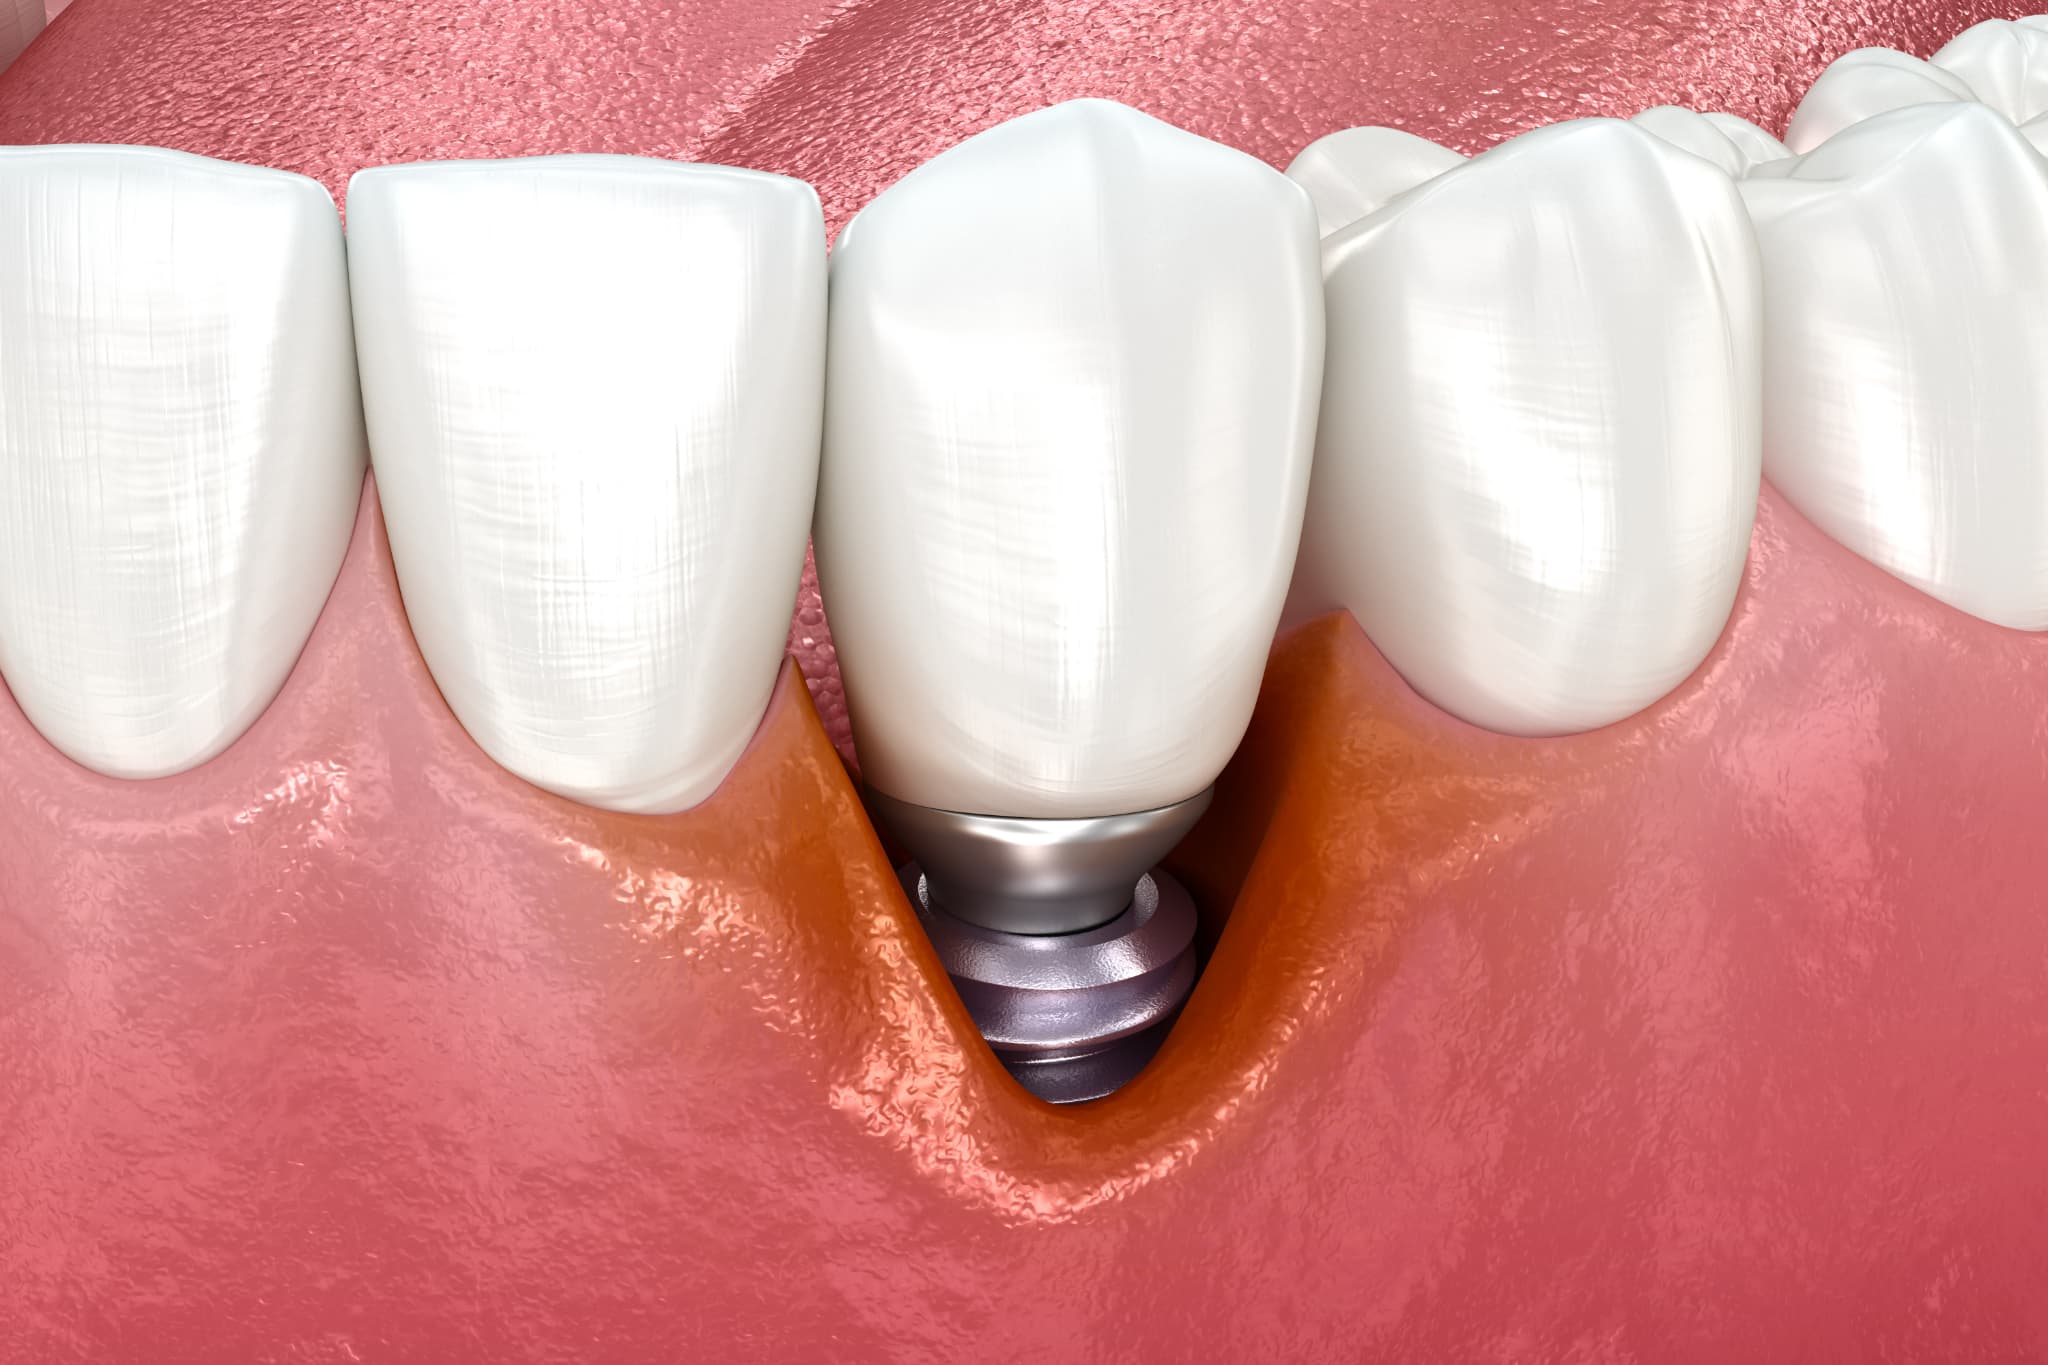

インプラント周囲炎のイメージ

インプラント周囲炎とは

インプラント周囲炎とは、インプラントを支える骨や周囲の組織に炎症が生じる状態を指します。インプラントの周囲に細菌が繁殖し、歯ぐきの腫れや出血、さらに進行すると骨が溶けてしまうこともあります。